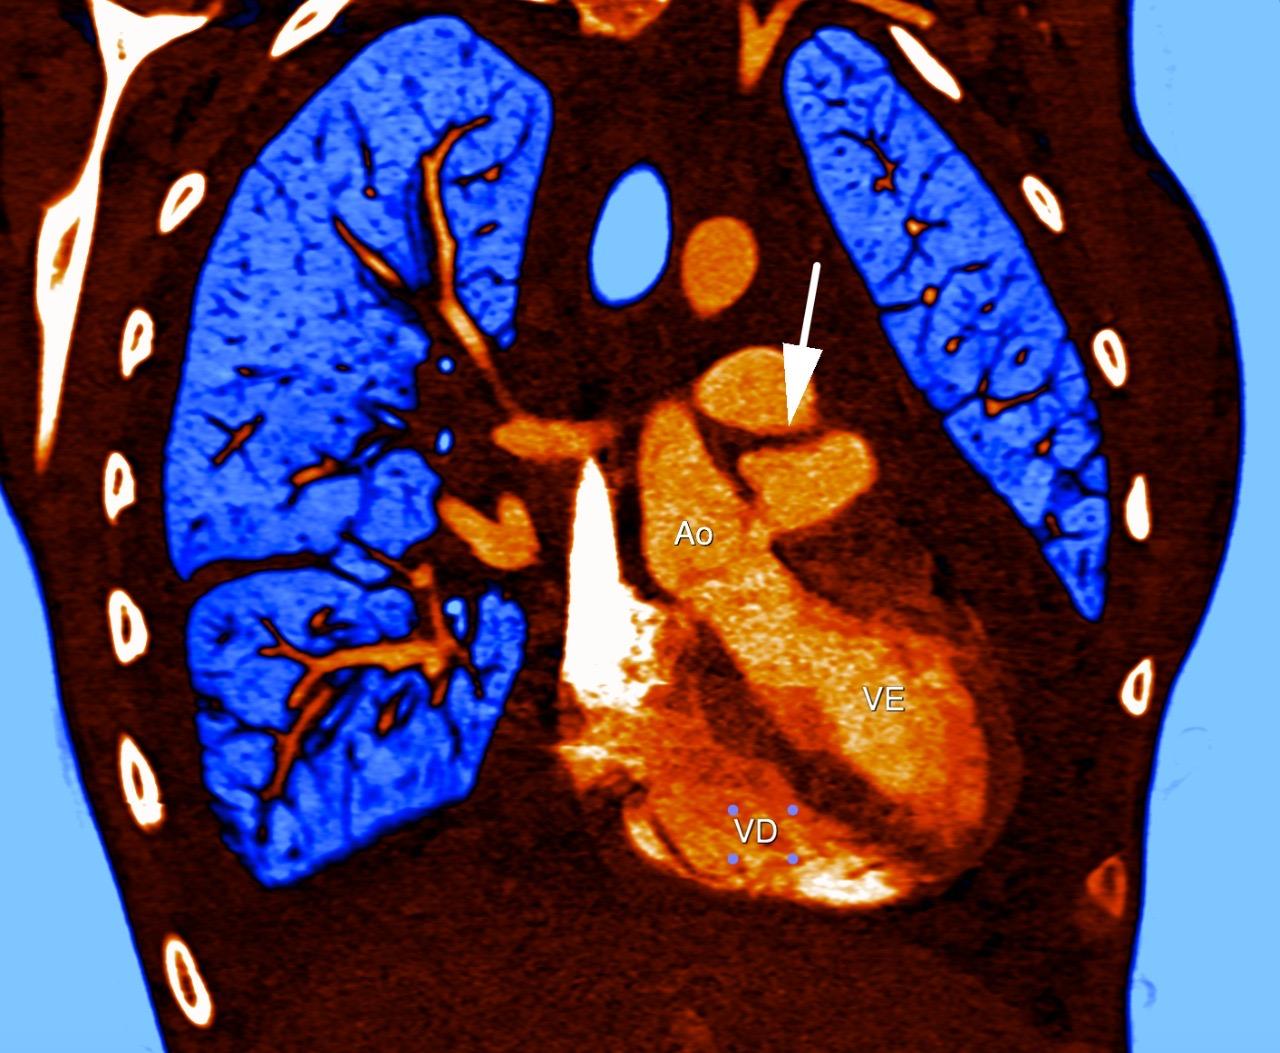

O que vemos nessa imagem???↓↓↓↓↓↓Resposta:O aneurisma do seio de Valsava é uma condição rara, que geralmente só causa sintomas após sua ruptura. É ocasionado pela separação ou pela falta de fusão e…